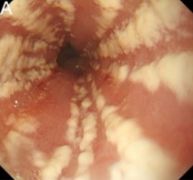

- Esophagus: Esophageal candidiasis

Esophageal candidiasis

- CMV esophagitis

- HSV esophagitis

- Local candidiasis is primarily clinically diagnosed based on lesion characteristics and appearance

- Confirmatory tests: KOH preparation of lesion scrapings, vaginal wet mount, culture, or endoscopic biopsy reveal budding yeast with pseudohyphae